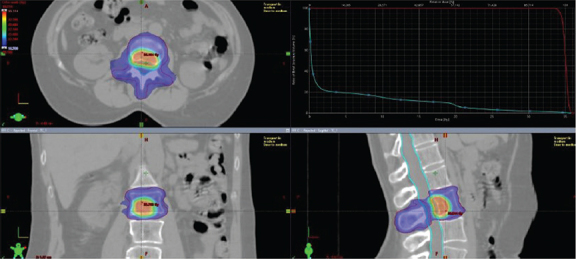

背景:高达75%的转移性乳腺癌(MBC)病例发生骨转移。成像技术的进步现在允许更早的检测,甚至在低转移期。放射治疗(RT)越来越多地用于无症状且≤5个骨病变的患者,但剂量和靶体积的标准化指南仍然缺乏。本研究评估了同时集成增强(SIB)使用调强放疗(IMRT)向宏观骨病变提供消融剂量的结果。方法:本回顾性研究分析了2014年1月至2022年1月期间接受sibb - imrt治疗的骨转移性MBC患者。主要终点是无局部进展(FFLP);次要终点包括放疗后疾病进展(DP-AR)和总生存期(OS)。根据年龄、免疫表型和治疗线进行亚组分析。结果:在954例接受RT治疗的患者中,85例接受了sibb - imrt (6- 8gy /分次,5个分次)。中位随访时间为41个月。19例(22.4%)为单一骨转移,23.5%为少转移,54.1%为多转移。中位FFLP为17个月;只有7%的SIB部位出现局部复发。DP-AR为13.2个月,中位OS为82.7个月。局部复发与年龄、免疫表型或全身治疗没有明显的相关性。免疫表型显著影响DP-AR (p = 0.002),而DP-AR和OS与局部进展无显著相关性。解释:sibb - imrt治疗MBC骨转移是可行和有效的,具有促进局部控制和最小毒性。有必要进行前瞻性研究,以优化剂量递增和探索与全身治疗的协同效应。

Background: Bone metastases occur in up to 75% of metastatic breast cancer (MBC) cases. Advances in imaging now allow earlier detection, even during the oligometastatic phase. Radiotherapy (RT) is increasingly used in asymptomatic patients with ≤5 bone lesions, however standardised guidelines for dose and target volumes remain lacking. This study evaluates the outcomes of a simultaneous integrated boost (SIB) using intensity-modulated radiotherapy (IMRT) to deliver ablative doses to macroscopic bone lesions.

Methods: This retrospective study analysed MBC patients treated with SIB-IMRT for bone metastases between January 2014 and January 2022. The primary endpoint was freedom from local progression (FFLP); secondary endpoints included disease progression after radiotherapy (DP-AR) and overall survival (OS). Subgroup analyses were performed according to age, immunophenotype, and line of therapy.